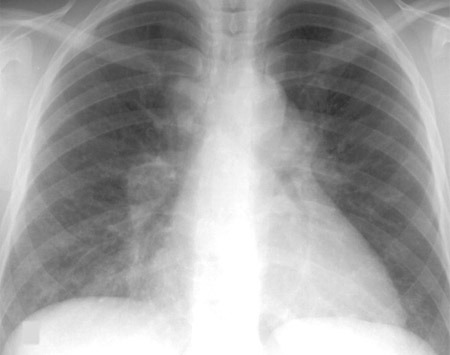

RT de fibrosis masiva progresiva debido a exposición a la sílice o al carbón

De la colección personal de Kenneth D. Rosenman, Michigan State University